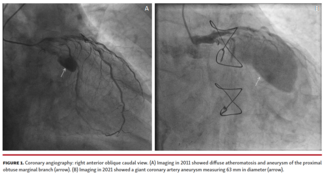

Petros Zampakis, MD, PhD; Periklis Davlouros, MD, PhD; Grigorios Tsigkas, MD, PhD; Georgis Vasilagkos, MS

A 78-year-old man with chronic atrial fibrillation, diabetes mellitus, and prior coronary artery bypass grafting (CABG) was admitted for coronary angiography due to severe aortic valve stenosis.